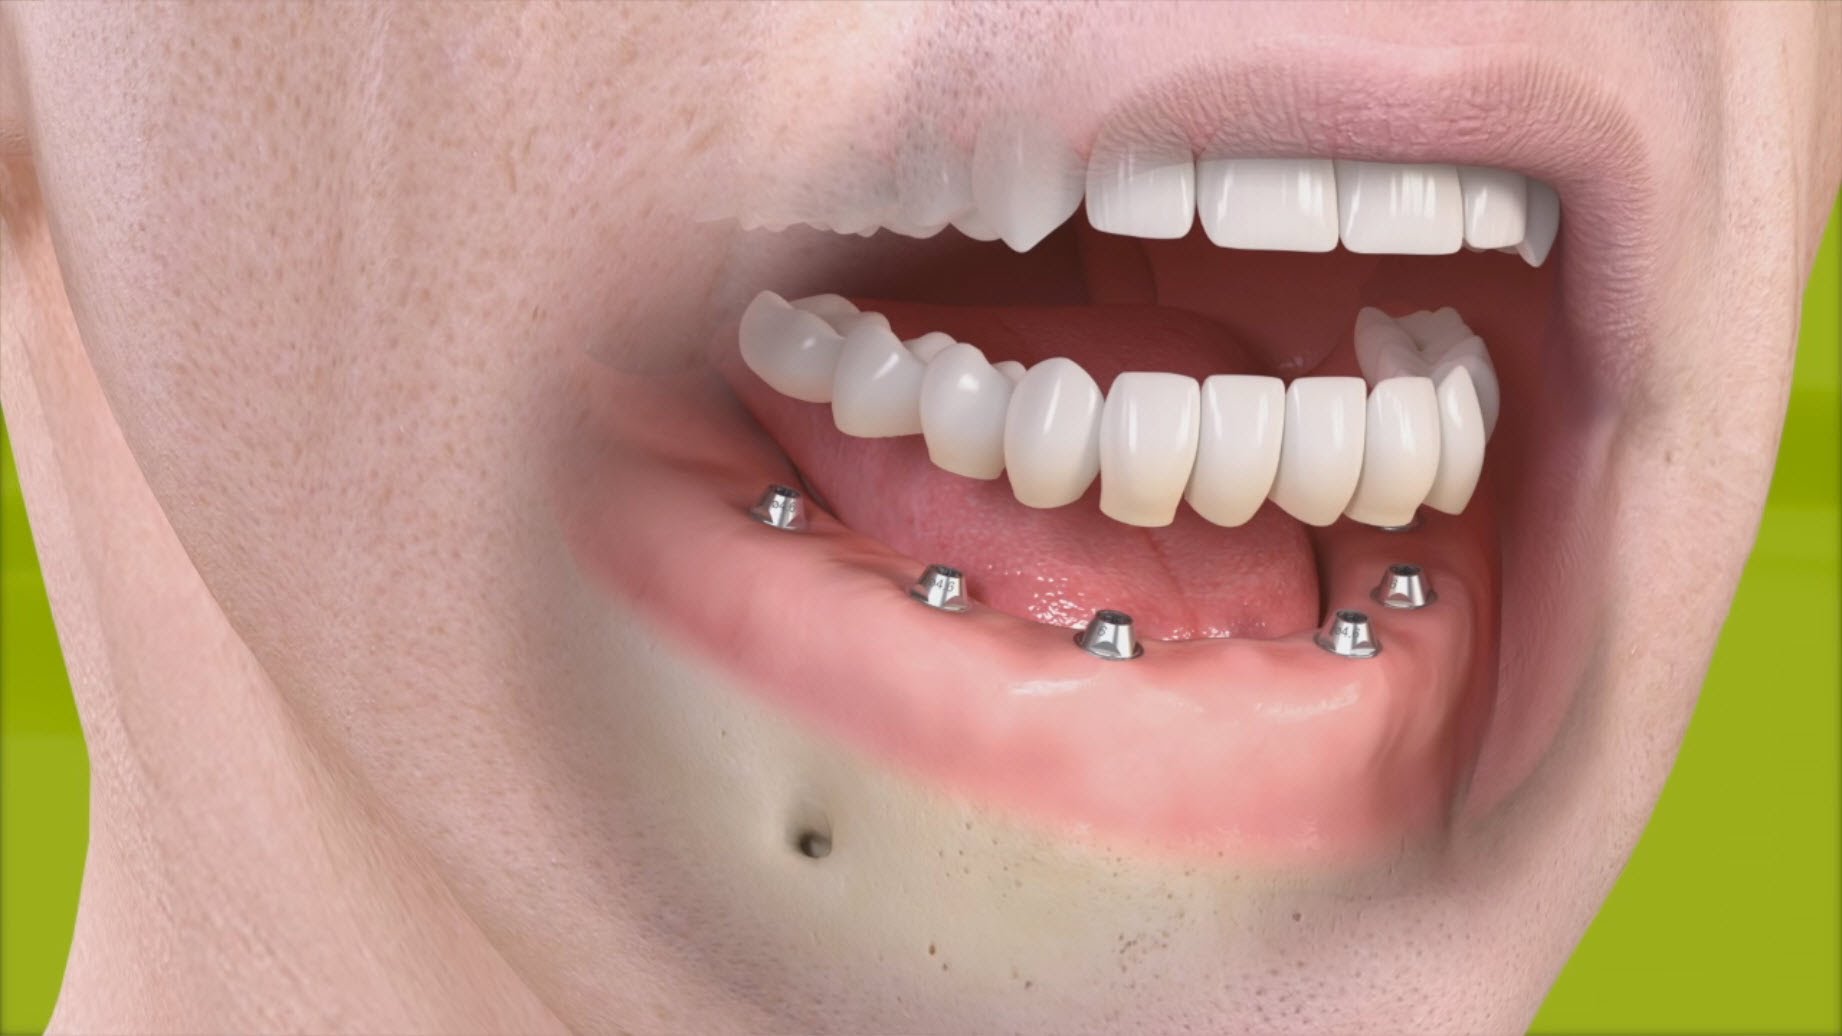

Tipos de rehabilitaciones implanto-soportadas

Cada paciente es único y diferente, por lo que la elección de un tratamiento u otro se verá condicionado por sus características y sus necesidades. En función del número de ausencias dentarias, las opciones terapéuticas varían sensiblemente.

EDENTULISMO PARCIAL

Coronas unitarias. Cuando es sólo un diente el que se ha perdido.

Puente sobre implantes. Cuando al menos son dos los implantes que se utilizan como punto de anclaje para remplazar las ausencias dentarias. El número de implantes que se utilicen como medio de apoyo de la futura prótesis será directamente proporcional a las ausencias dentarias.

EDENTULISMO TOTAL

Sobredentadura. Es importante destacar que esta modalidad de tratamiento se perfila como una opción REMOVIBLE, es decir, una vez colocados los implantes (su número varía desde un mínimo de 2 a un máximo de 4 en la mandíbula y un mínimo de 4 en el maxilar) la prótesis se asentará y ajustará sobre ellos de una manera firme y estable, pero el paciente podrá retirarla siempre que lo desee. Relativamente voluminosa, la prótesis repone la totalidad de los dientes ausentes así como los tejidos perdidos como consecuencia del proceso de reabsorción ósea que se desencadena tras la pérdida dentaria.

Prótesis híbrida. Modalidad FIJA de tratamiento. A diferencia de la anterior, el paciente no podrá retirarla, será el odontólogo el encargado de hacerlo siempre que fuese necesario. Exige un mínimo de 4 hasta un máximo de 6 implantes en la mandíbula y un mínimo de 6 implantes en el maxilar. La prótesis irá directamente atornillada a los pilares, reponiendo la totalidad de los dientes ausentes y mínimamente los tejidos perdidos.

Prótesis fija. Como su propio nombre indica, se trata de una modalidad FIJA de tratamiento. Exige un mínimo de 6 hasta un máximo de 8 implantes en la mandíbula y un mínimo de 6 hasta un máximo de 8 implantes en el maxilar. La prótesis podrá ir atornillada o cementada, reponiendo EXCLUSIVAMENTE la totalidad de los dientes ausentes.